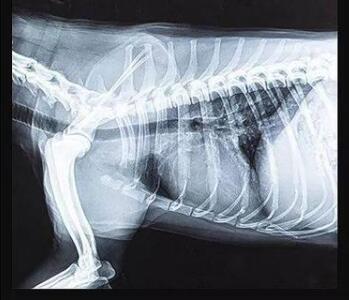

傳統(tǒng)的平板探測器,相當(dāng)于普通攝像機(jī),對于拍攝急促呼吸狀態(tài)下的寵物,成像效果存在著明顯缺陷。而新一代寵物平板探測器,宛如高速攝像機(jī),能夠清晰記錄動物每一個精準(zhǔn)瞬間。

寵物dr專用平板拍攝效果